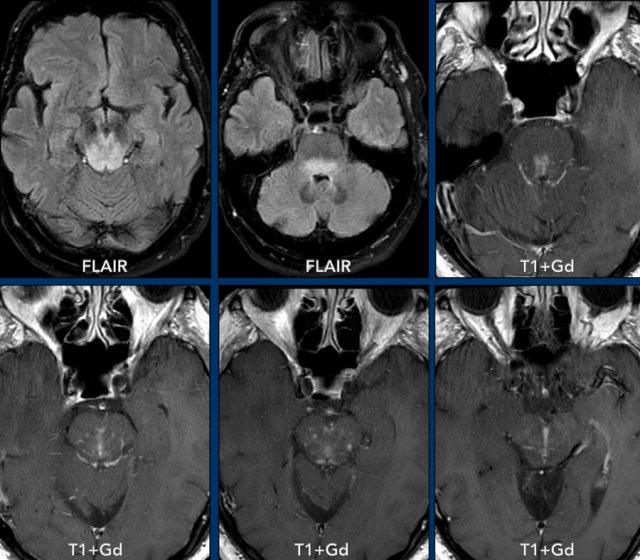

Bệnh nhân này có tiền sử ung thư phổi và nhập viện với các triệu chứng đau đầu và chậm chạp về tâm thần.

Hãy quan sát các hình ảnh trước rồi tiếp tục đọc.

Hình ảnh

Ghi nhận nhiều tổn thương ngấm thuốc dạng vòng viền liên thông nhau kèm phù não xung quanh ở bán cầu phải.

Vỏ bao tương đối mỏng và đều với hạn chế khuếch tán ở trung tâm.

Có sự lan rộng đến não thất bên phải kèm ngấm thuốc của lớp lót não thất (mũi tên).

Lưu ý thêm hạn chế khuếch tán tại tam giác não thất bên trái.

Nhiều người cho rằng đây là bệnh di căn do tiền sử bệnh, nhưng các dấu hiệu hình ảnh điển hình hơn cho áp xe não kèm viêm não thất, và đây chính là chẩn đoán cuối cùng được xác nhận.